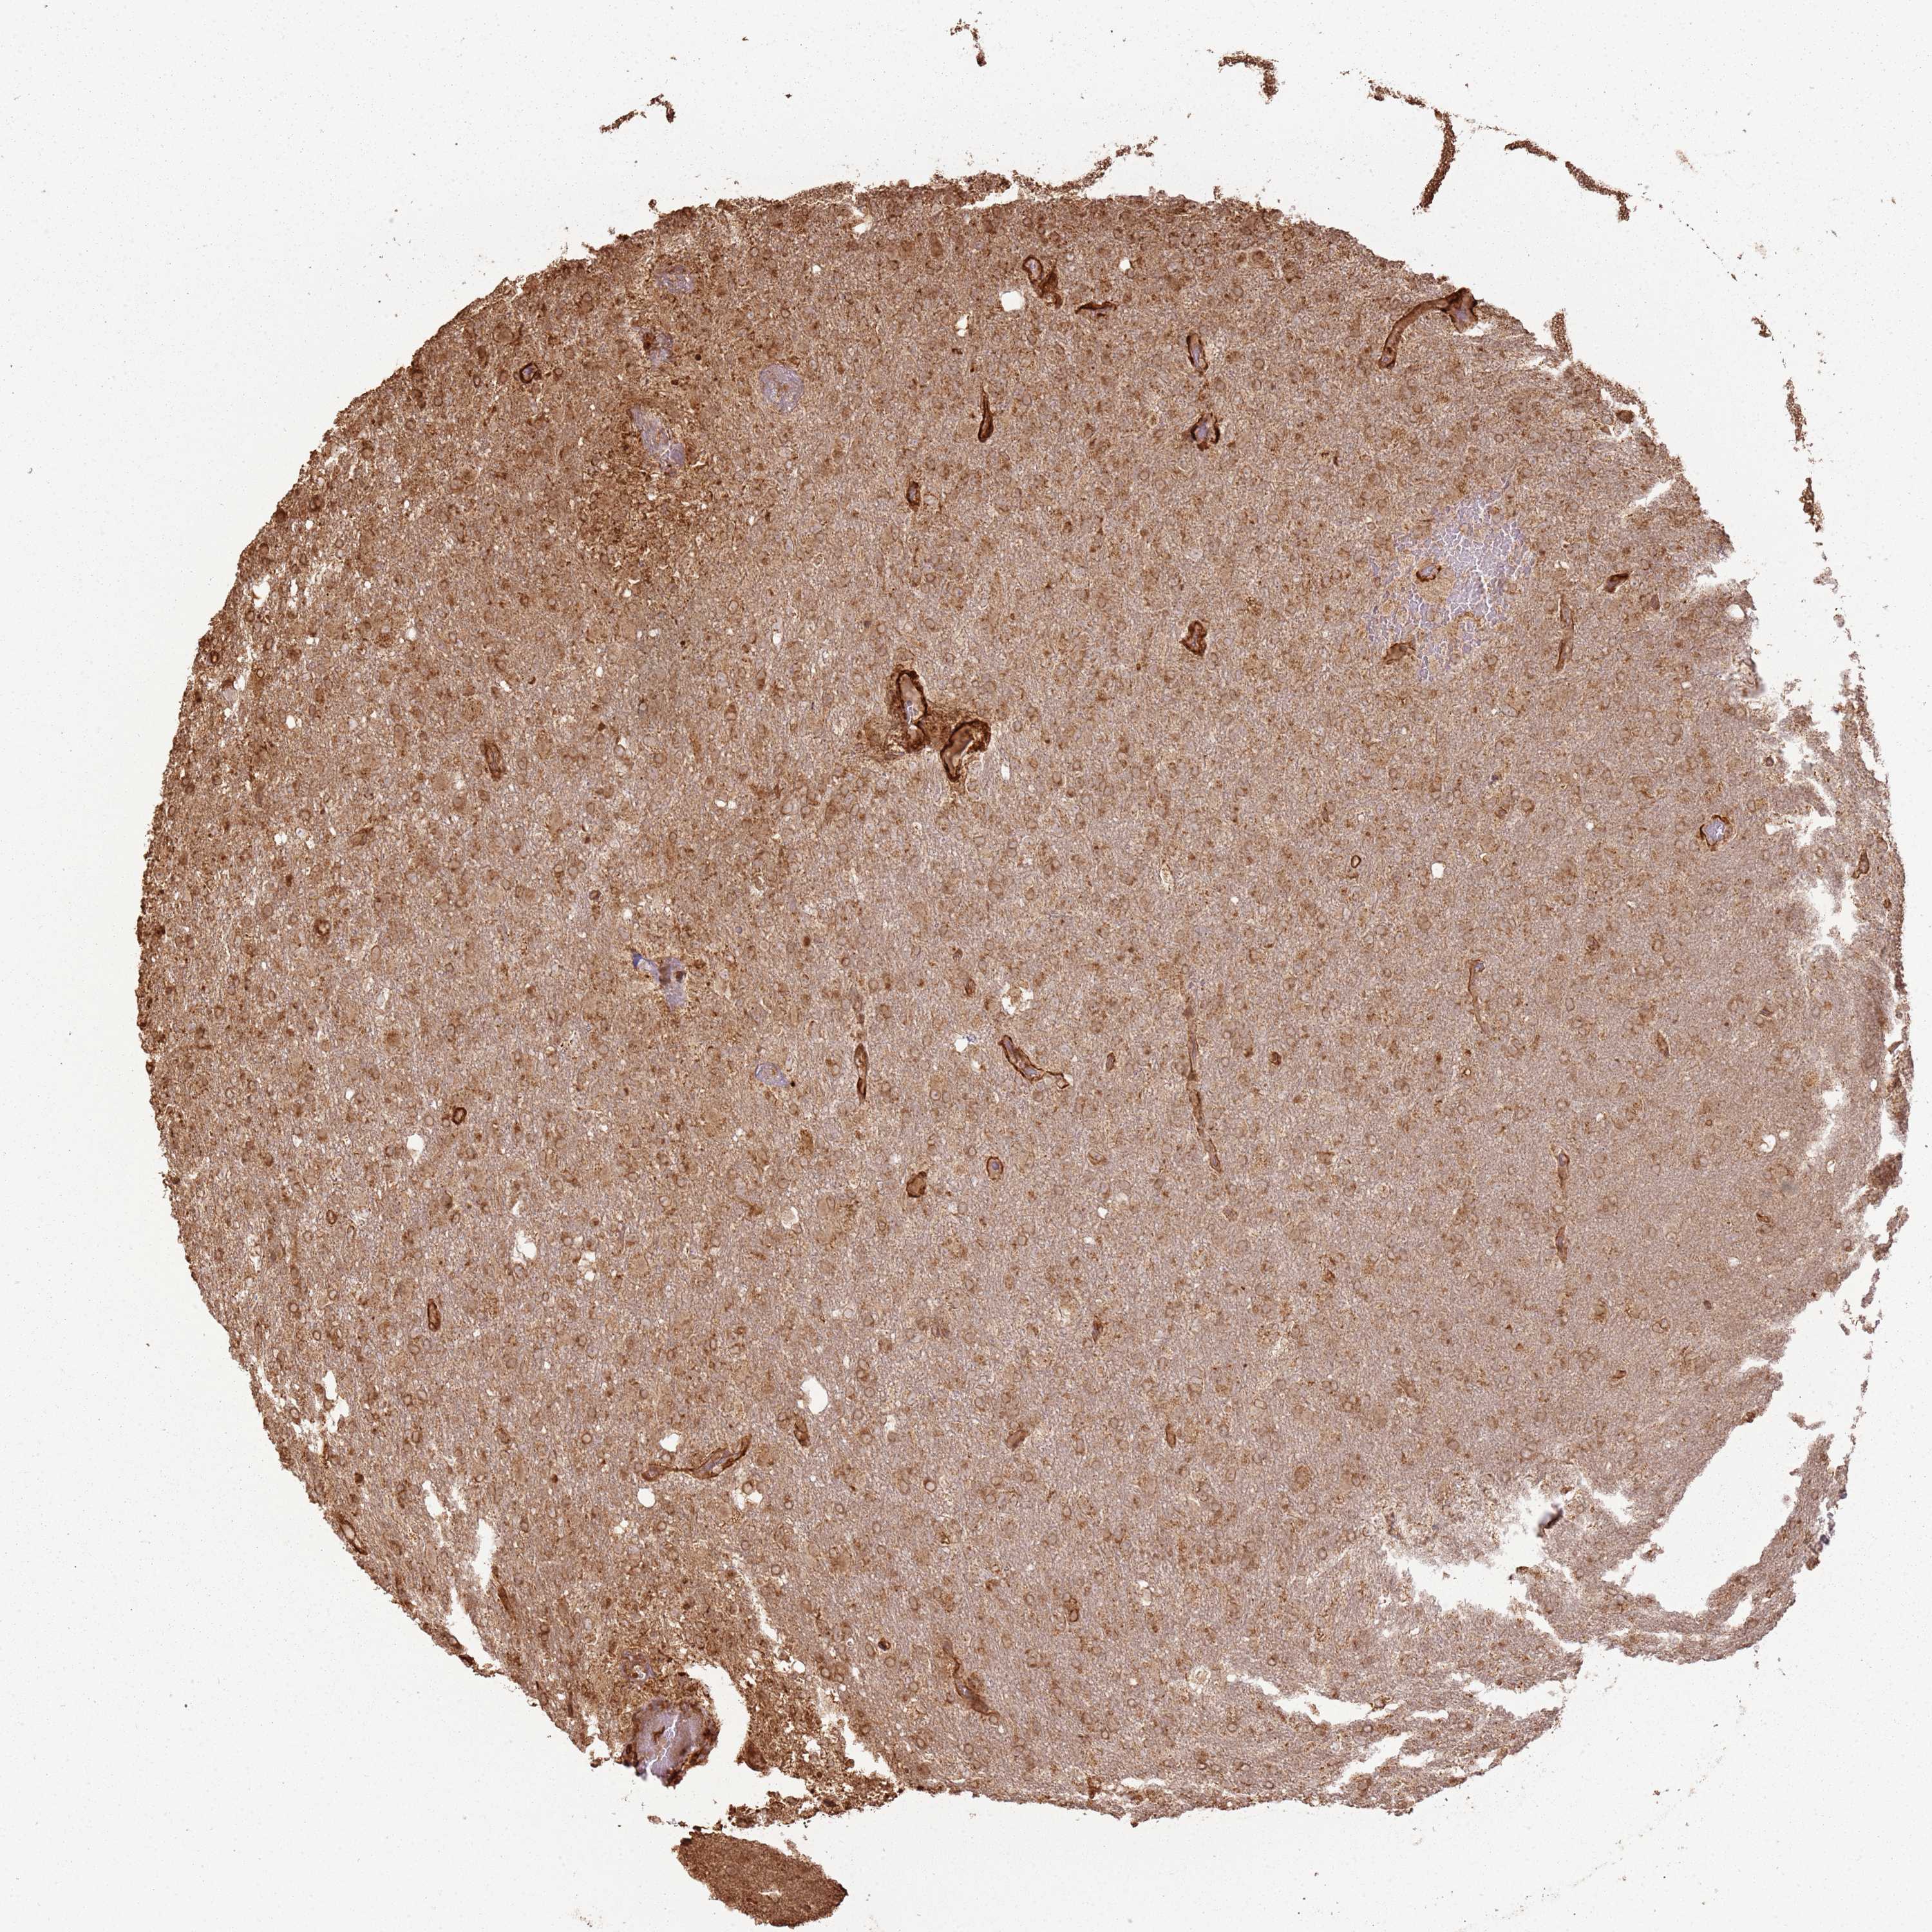

GLIOMA - Protein expressioni

A mouse-over function shows sample information and annotation data. Click on an image to view it in a full screen mode. Samples can be filtered based on level of antibody staining by selecting one or several of the following categories: high, medium, low and not detected. The assay and annotation is described here.

Note that samples used for immunohistochemistry by the Human Protein Atlas do not correspond to samples in the TCGA dataset.

Antibody stainingi

Antibody staining in the annotated cell types in the current human tissue is reported as not detected, low, medium, or high, based on conventional immunohistochemistry profiling in selected tissues. This score is based on the combination of the staining intensity and fraction of stained cells.

Each image is clickable and will lead to virtual microscopy that enables deeper exploration of all samples and also displays staining intensity scores, fraction scores and subcellular localization as well as patient and tissue information for each sample.

Antibody HPA047166

Staining

High

Medium

Low

Not detected

Intensity

Strong

Moderate

Weak

Negative

Quantity

>75%

75%-25%

<25%

None

Location

Nuclear

Cytoplasmic/membranous

Cytoplasmic/membranous,nuclear

Glioma, malignant, High grade

Glioma, malignant, Low grade